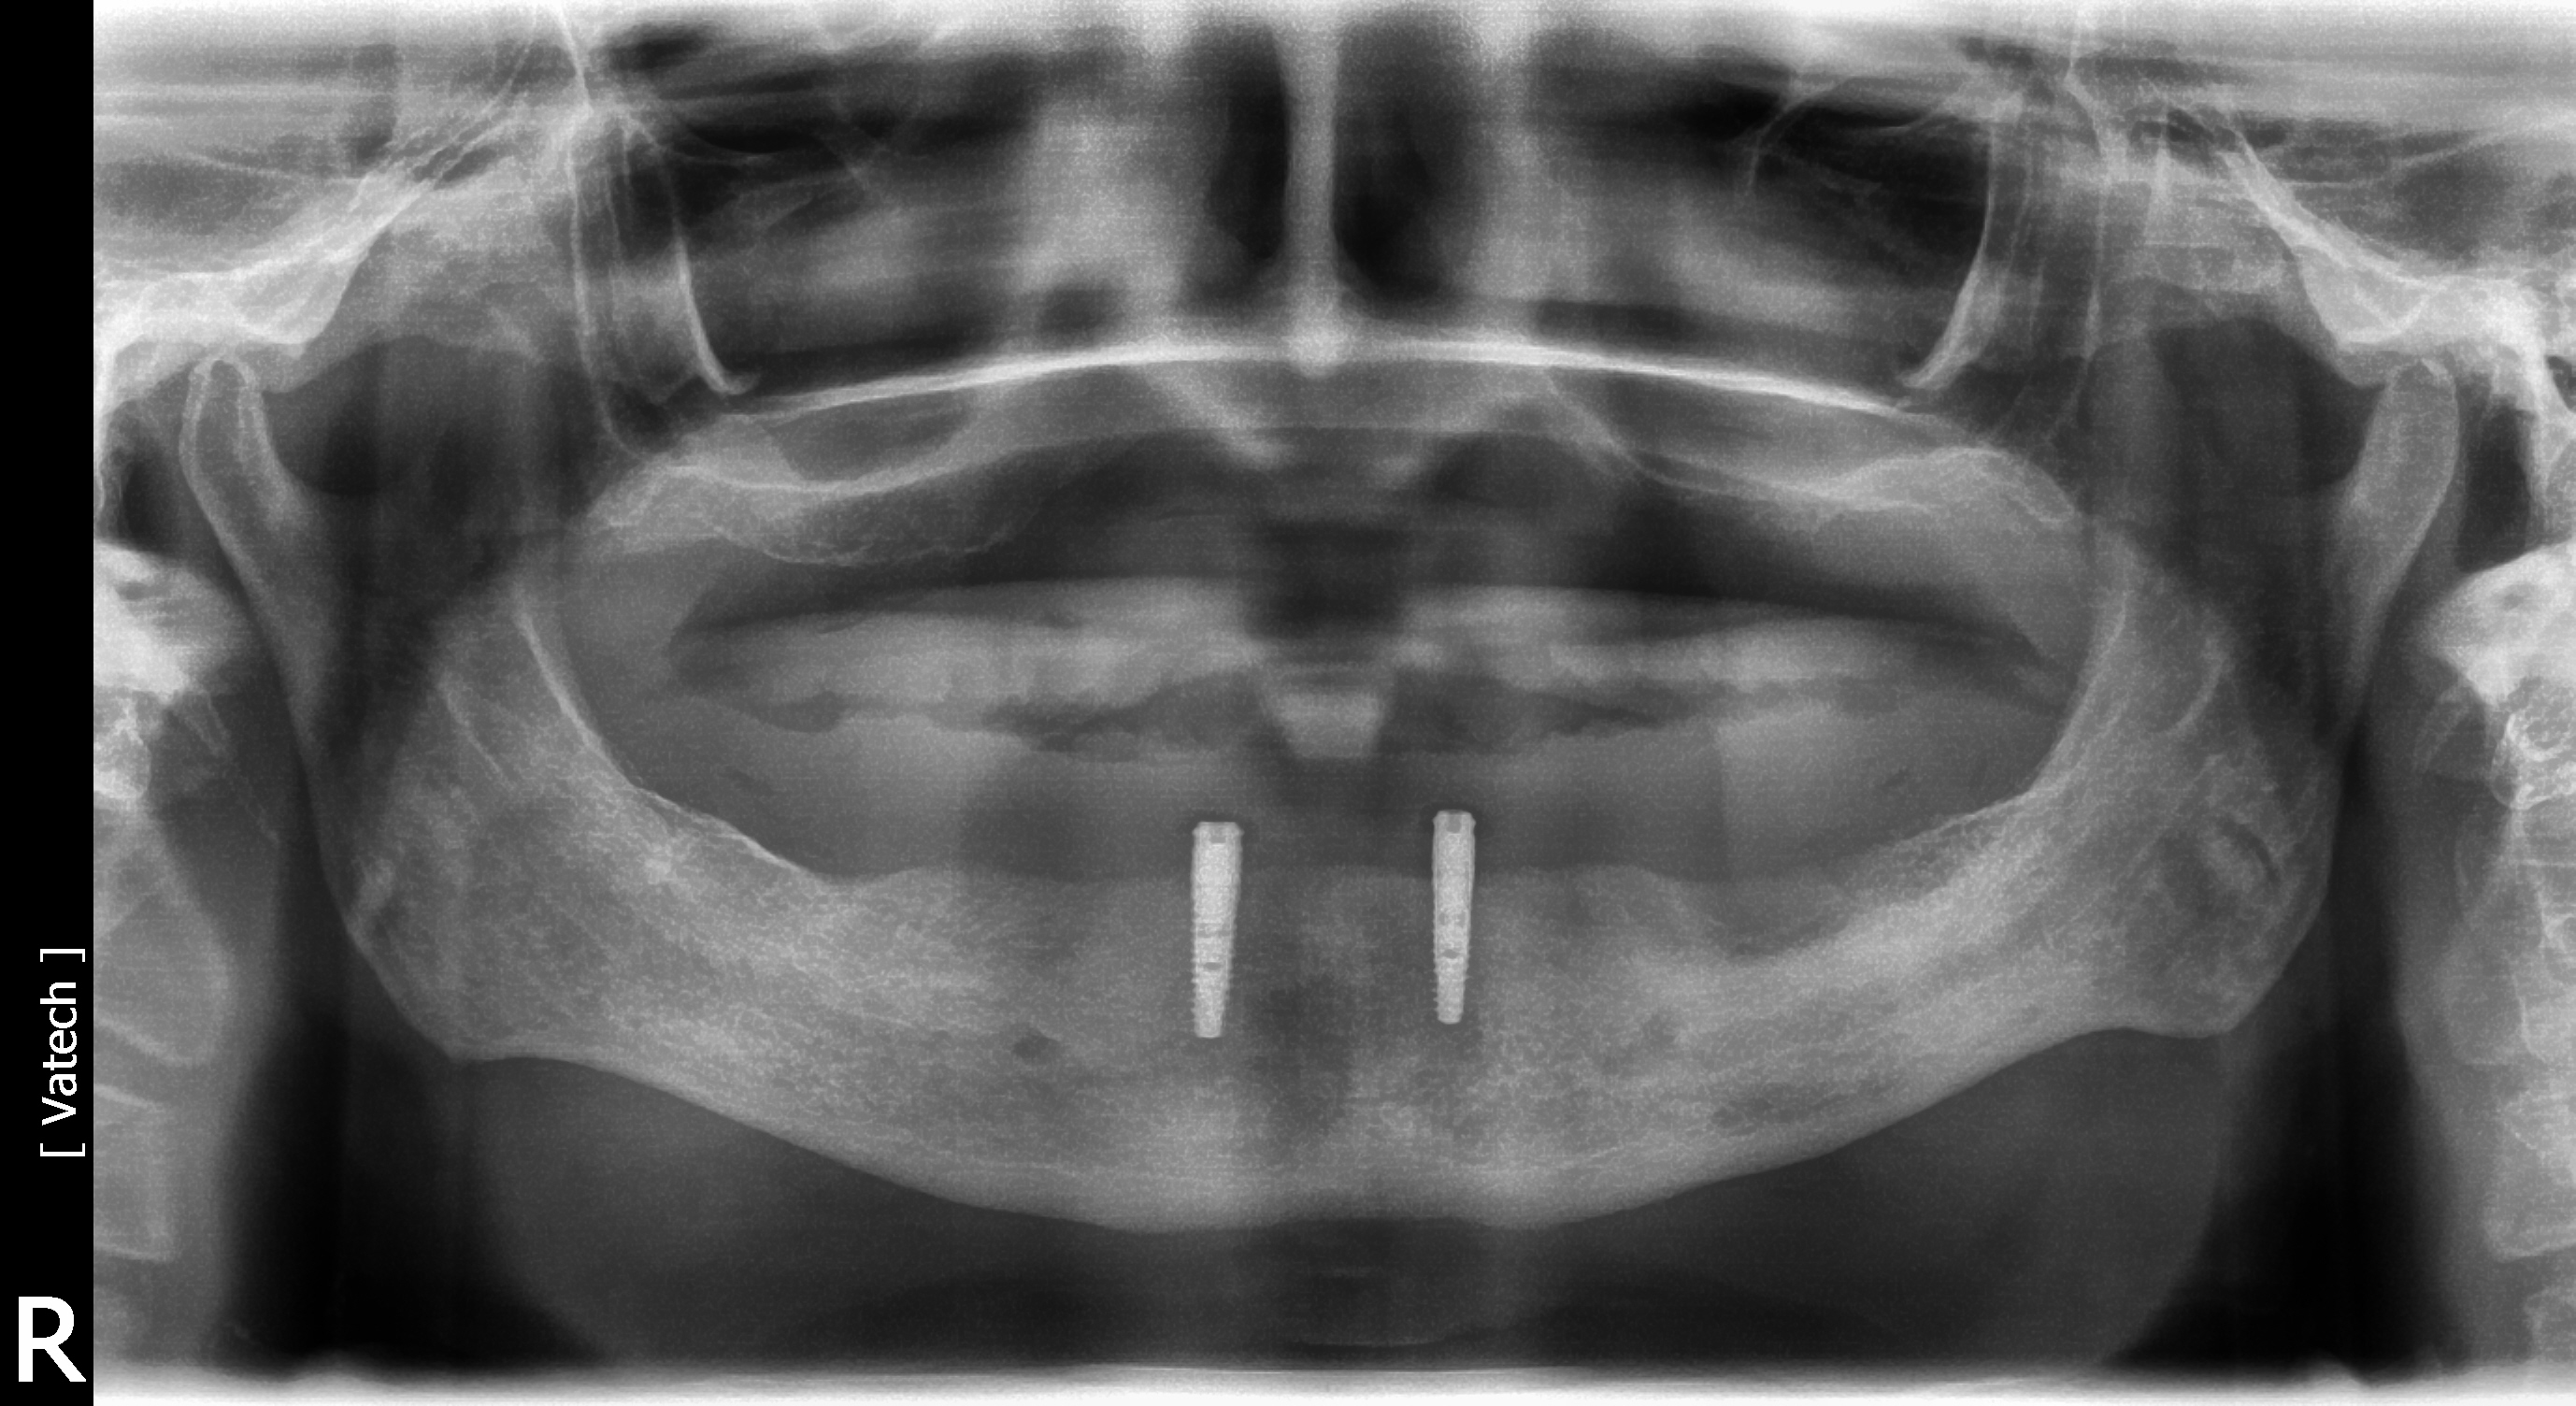

A 75-year-old man presented with a failing dentition (Figure 2 and Figure 3). Upon evaluation, the patient indicated that he desired a new maxillary complete denture and a mandibular overdenture, and the clinician discussed with him the possible option of two or four implants for his mandibular arch. However, upon further analysis, the patient was found to have extensive periapical lesions in the mandibular left first molar region. Additionally, the patient expressed that, owing to his advanced age, he was concerned about surgical complexity and the cost of reconstruction with four implants, and stated a preference for a simpler and more expedited treatment.

The patient chose the two-implant overdenture option with implants placed at the time of the tooth extractions. The clinician discussed with the patient that additional implant placements could be undertaken at a later date, and the patient was pleased to learn that he had this future option. Teeth were extracted and two 3.4 x 12 implants (Biomet Osseotite®, Zimmer Biomet) were placed in the B and D positions in the interforaminal region of the anter-ior mandible (Figure 4). Implants placed in the indicated regions permit additional implants to be placed distally, in the mandibular first molar or interforaminal A and E positions. After osseointegration, stud-style abutments (LOCATOR R-Tx, Zest Dental Solutions) were placed and a new prosthesis fabricated (Figure 5). The patient was pleased with the final result.

Fig 3. Radiograph showing extensive periodontal disease. After being presented with the option to have two or four implants, the patient chose to have two implants. Because he wanted the option to have additional implants in the future, the implants were placed in regions that would permit placement of additional implants.

Figure 3